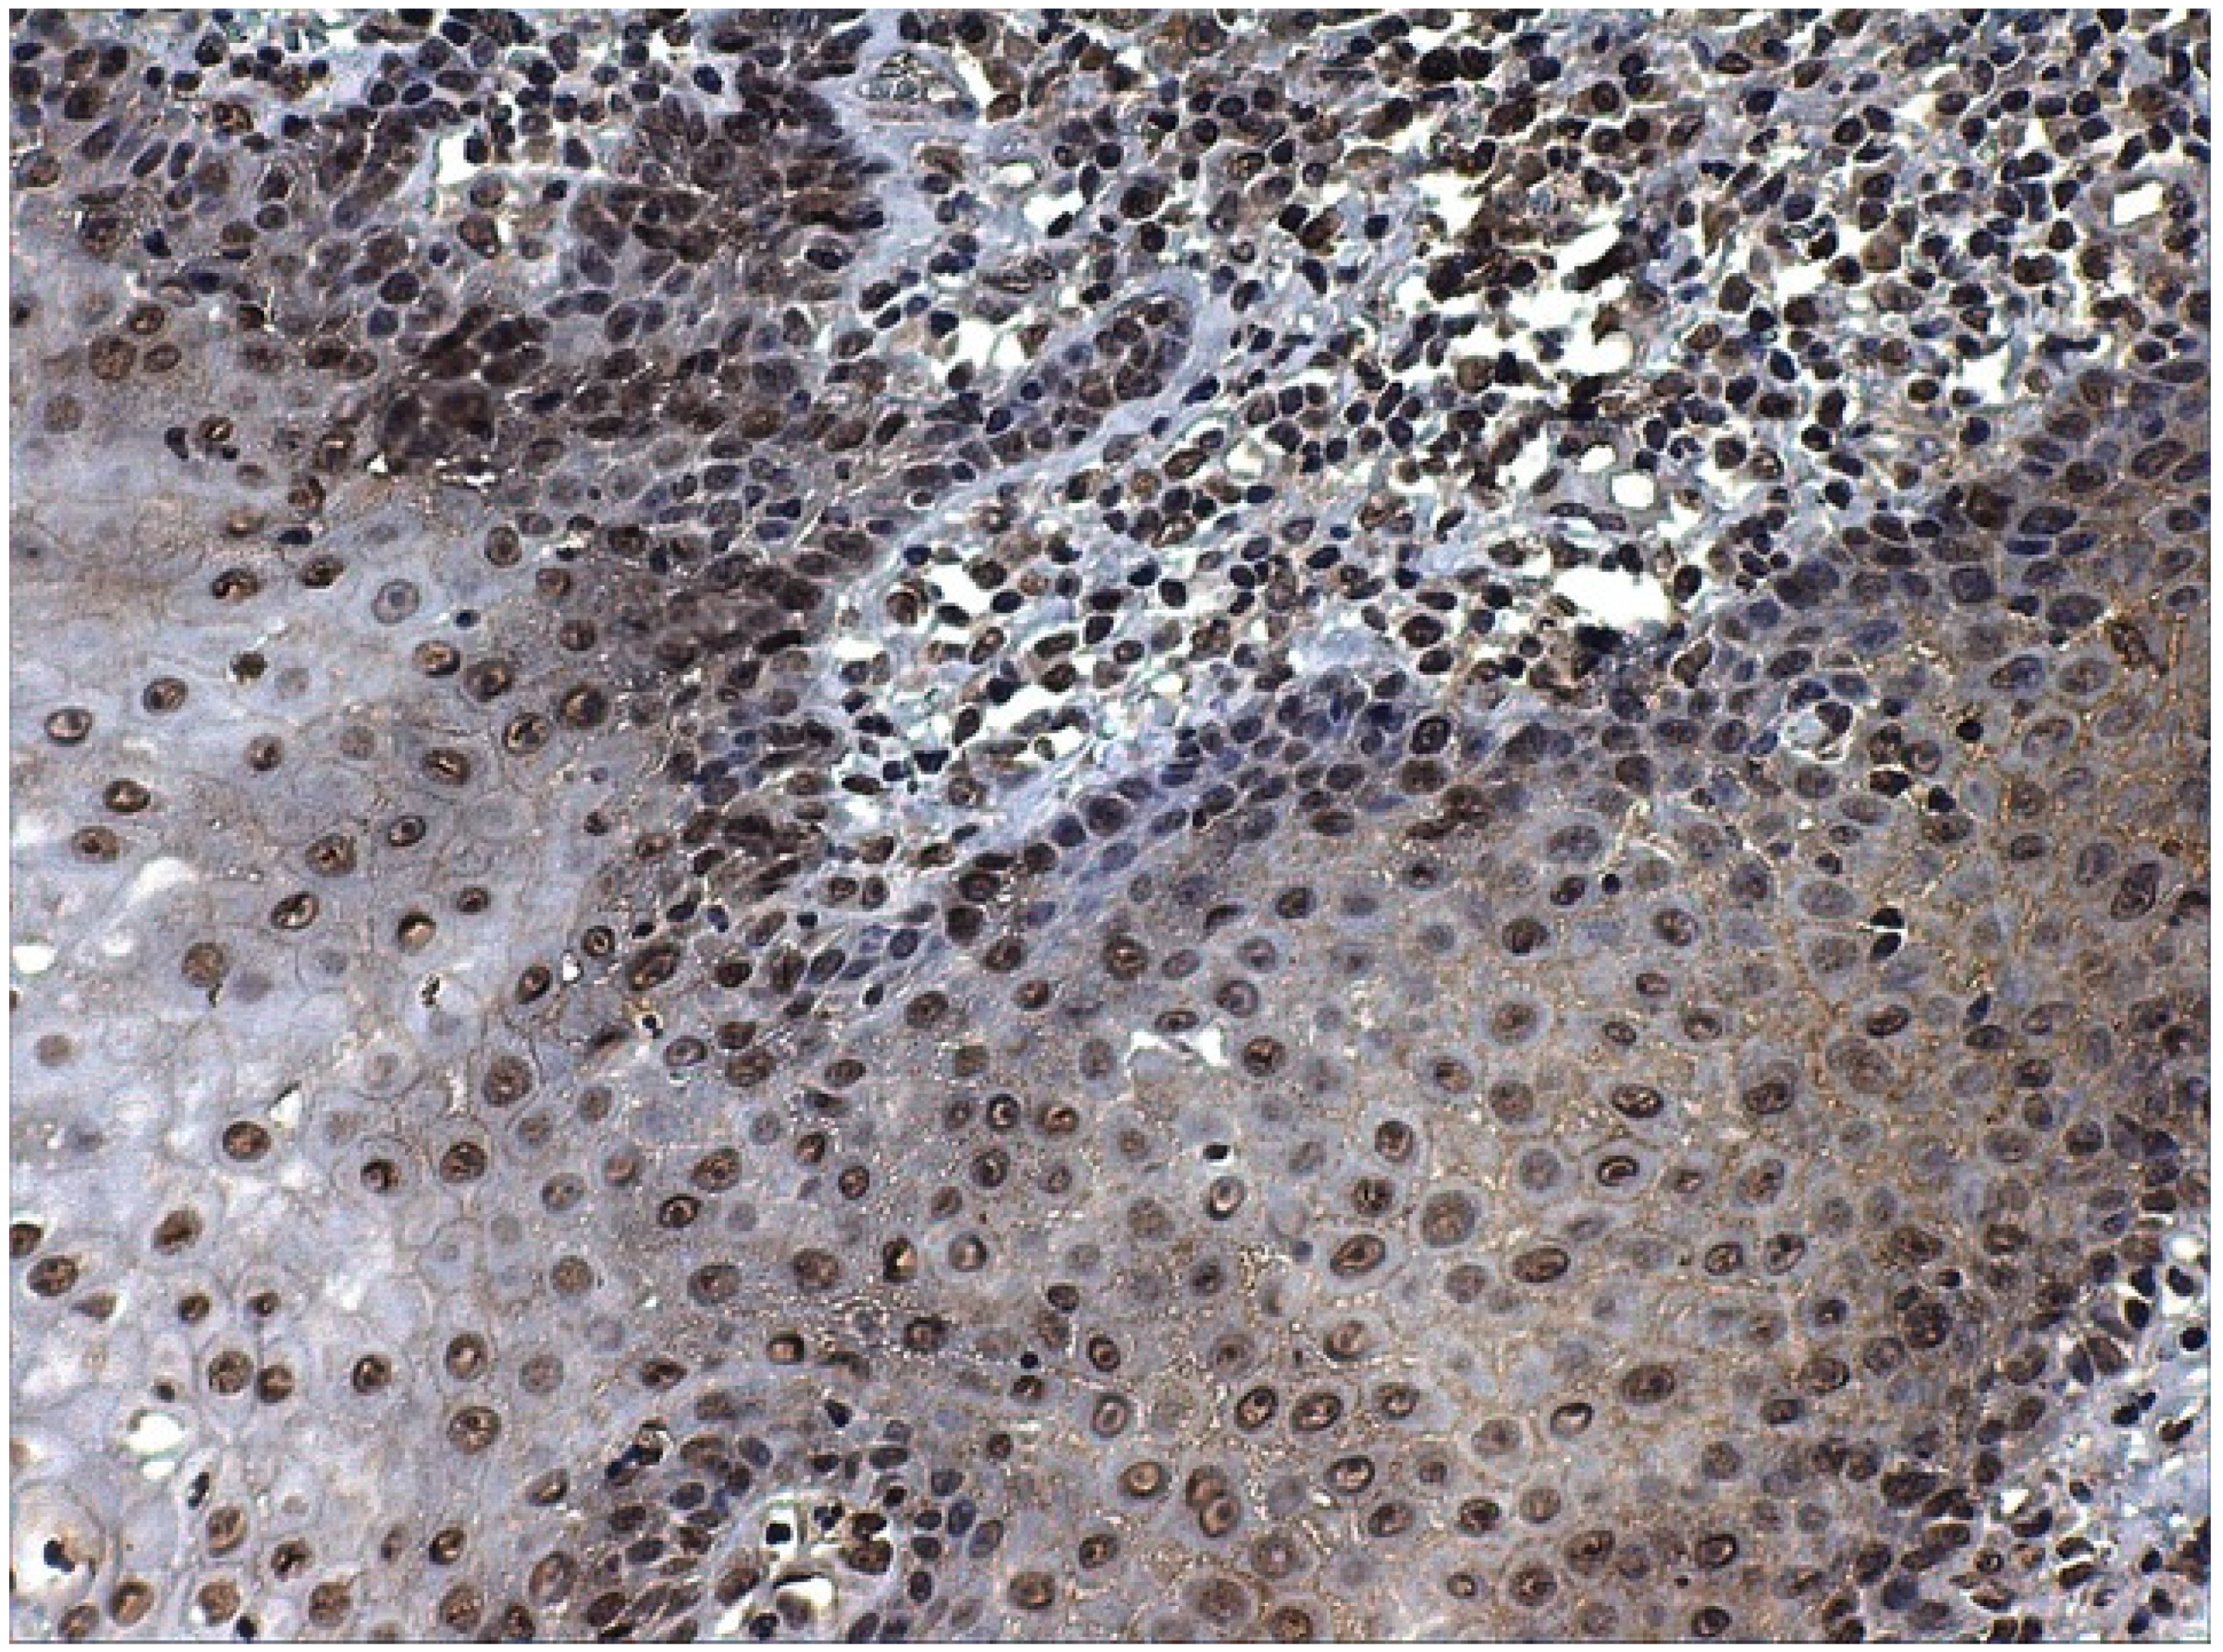

- Brener, S.; González-Moles, M.A.; Tostes, D.; Esteban, F.; Gil-Montoya, J.A.; Ruiz-Avila, I.; Bravo, M.; Muñoz, M. A role for the substance P/NK-1 receptor complex in cell proliferation in oral squamous cell carcinoma. Anticancer Res. 2009, 29, 2323–2329. [Google Scholar]

- González-Moles, M.A.; Brener, S.; Ruiz-Avila, I.; Gil-Montoya, J.A.; Tostes, D.; Bravo, M.; Esteban, F. Substance P and NK-1R expression in oral precancerous epithelium. Oncol. Rep. 2009, 22, 1325–1331. [Google Scholar] [CrossRef][Green Version]

- Esteban, F.; Gonzalez-Moles, M.A.; Castro, D.; Martin-Jaen, M.d.M.; Redondo, M.; Ruiz-Avila, I.; Muñoz, M. Expression of substance P and neurokinin-1-receptor in laryngeal cancer: Linking chronic inflammation to cancer promotion and progression. Histopathology 2009, 54, 258–260. [Google Scholar] [CrossRef] [PubMed]

- Isorna, I.; Esteban, F.; Solanellas, J.; Coveñas, R.; Muñoz, M. The substance P and neurokinin-1 receptor system in human thyroid cancer: An immunohistochemical study. Eur. J. Histochem. 2020, 64, 3117. [Google Scholar] [CrossRef] [PubMed]